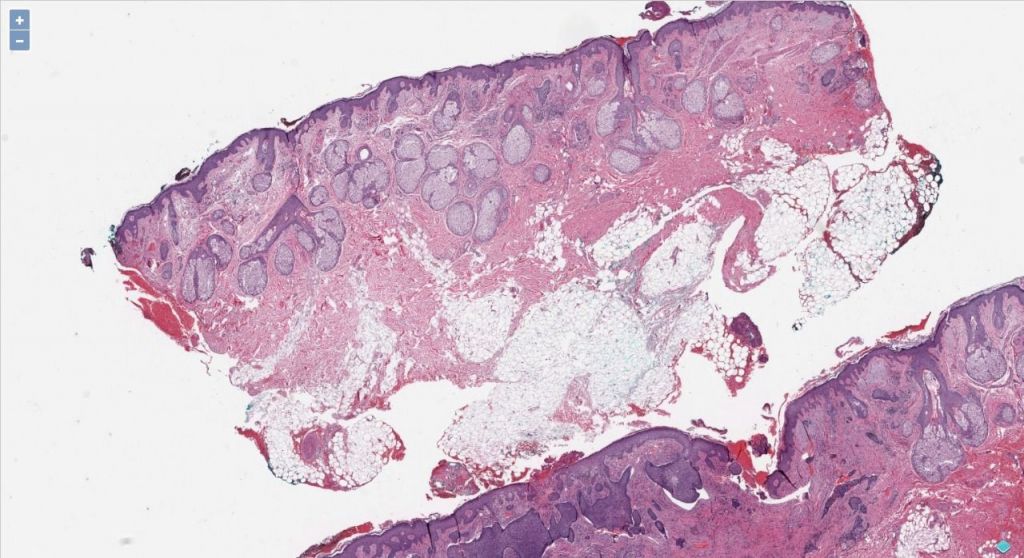

In this article, we will dissect how to approach the problems like classification and segmentation for the Whole Slide Images (WSI) that can provide insights to pathologists quickly!

A brief about WSI

Whole Slide Imaging, also known as virtual microscopy, aims to imitate microscopy in a computer-generated manner. Thus, archiving and applying image-based solutions is trouble-free.

The approaches explained below are generic and could have usage in different use-cases in pathology. We will look into both the classification and segmentation of WSI.